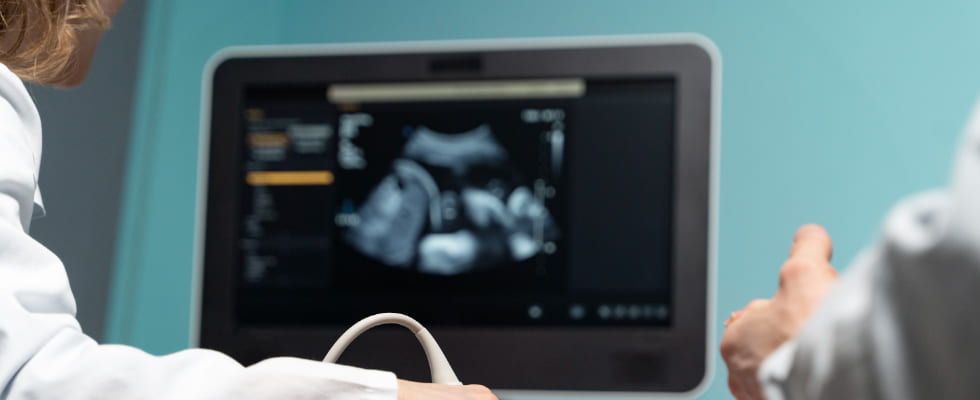

La ecografía morfológica es una prueba de diagnóstico prenatal que se realiza durante el segundo trimestre del embarazo, generalmente entre las semanas 18 y 22 de gestación. Esta ecografía evalúa el desarrollo y la anatomía del feto, permitiendo detectar posibles anomalías estructurales y malformaciones congénitas. Además, proporciona información detallada sobre el crecimiento fetal, la ubicación de la placenta y la cantidad de líquido amniótico, contribuyendo a un seguimiento exhaustivo del embarazo.

Se realiza mediante el uso de un transductor que emite ondas sonoras de alta frecuencia. Estas ondas sonoras rebotan en los tejidos del feto y crean imágenes detalladas en tiempo real. El procedimiento se lleva a cabo con la paciente acostada, y se aplica un gel conductor en el abdomen para mejorar la transmisión de las ondas sonoras. Las imágenes obtenidas permiten evaluar la anatomía y el desarrollo del feto, detectando posibles anomalías estructurales y proporcionando información crucial para el seguimiento del embarazo.